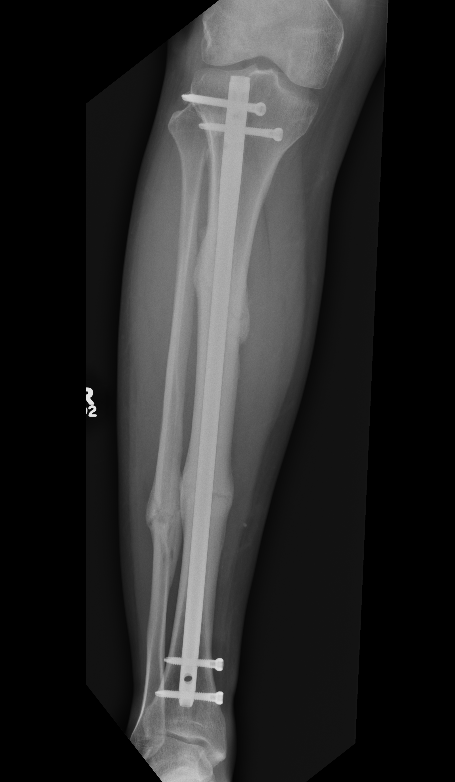

1.  IMN Tibia

Tibial Nail 1Tibial Nail 2